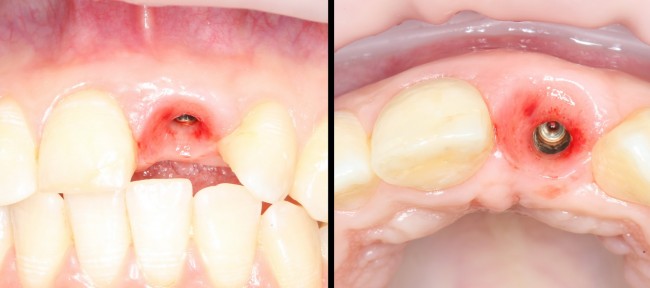

Через год после травмы, девушка обратилась в нашу клинику для восстановления отсутствующего зуба. К тому моменту у нее уже был временный съемный протез, изготовленный в вышеозначенном стоматологическом кабинете, ну и, вот какая клиническая картина:

Через 3 месяца мы готовы приступить к формированию десны. И каким-то невероятным образом, у нас получился даже избыток слизистой оболочки. Что, безусловно, очень даже хорошо:

По фотографии хорошо видно, как изменилась форма альвеолярного гребня после операции.

Ответственный момент. Делаем разрез и открываем имплант:

Как видите, вестибулярная стека импланта находится в новообразованной костной ткани. А это значит, что наша остеопластика удалась. Хотя, это еще нельзя назвать результатом нашей операции.

Ставим формирователь десны. Затем, Давид окончательно формирует десну с помощью временной коронки. После его формирования слизистая выглядит примерно так:

а это уже очень близко к тому, что мы хотим получить в результате лечения. Именно поэтому не стоит игнорировать временные коронки, особенно в эстетически значимой зоне. И, особенно, в ответственных случаях.